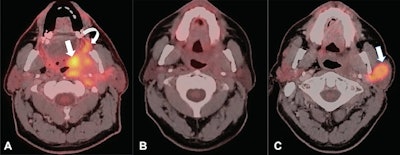

The prognosis for patients with locally advanced HNC is poor, with approximately 40% of patients experiencing recurrence. Surveillance imaging is performed to detect recurrence of disease before clinical symptoms and signs develop. Yet there is lack of high-level evidence to support its use to improve overall patient mortality rates, the authors wrote.

To elucidate the issue, the researchers identified 1,004 patients who underwent PET/CT, CT, and/or MRI for HNC between January 2012 and December 2017. The group included 902 patients with squamous cell carcinoma (SCC) HNC and 102 patients with non-SCC. Approximately 74% (666 of 902) of patients with SCC and 74% (75 of 102) of patients with non-SCC underwent surveillance imaging at least once.

According to the findings, a lower mortality rate was associated with SCC in patients who underwent surveillance imaging for regionalized cancer stage (hazard ratio [HR], 0.55; p = 0.005) and distant cancer stage (HR, 0.40; p = 0.01) compared with those without surveillance imaging. The median years of survival was 3.76 years for the surveillance imaging group and 2.89 years for the no-surveillance imaging group in patients with SCC.

"The surveillance imaging protective association was observed up to two years after treatment completion," Anzai and colleagues wrote.